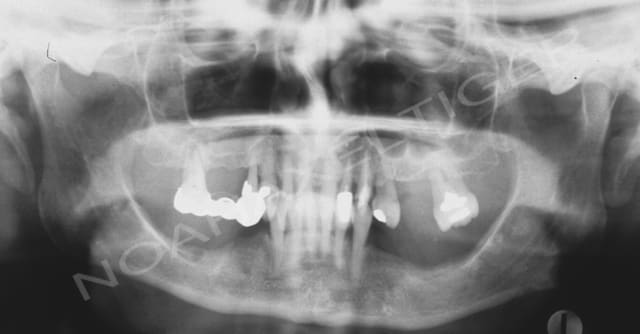

J'ai traité il ya de cela quelque temps un cas de réhabilitation globale sur terrain paro. Comme toi ikimine j'ai du faire face à un effondrement de DV, ce qui m'a amené à combiner paro, implanto, prothétique conventionnelle et occluso.

Voila les photos et radios initiales :

Opg initial pocr0a - Eugenol